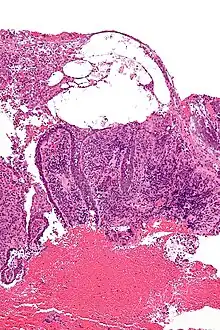

Micrograph of pemphigus vulgaris with the characteristic "tombstoning". H&E stain.

Pemphigus is an autoimmune disease caused by antibodies directed against both desmoglein 1 and desmoglein 3 present in desmosomes. Loss of desmosomes results in loss of cohesion between keratinocytes in the epidermis, and a disruption of the barrier function served by intact skin. The process is classified as a type II hypersensitivity reaction (in which antibodies bind to antigens on the body's own tissues). On histology, the basal keratinocytes are usually still attached to the basement membrane leading to a characteristic appearance called "tombstoning". Transudative fluid accumulates in between the keratinocytes and the basal layer (suprabasal split), forming a blister and resulting in what is known as a positive Nikolsky's sign. This is a contrasting feature from bullous pemphigoid, which is thought to be due to anti-hemidesmosome antibodies, and where the detachment occurs between the epidermis and dermis (subepidermal bullae). Clinically, pemphigus vulgaris is characterized by extensive flaccid blisters and mucocutaneous erosions. The severity of the disease, as well as the mucosal lesions, is believed to be directly proportional to the levels of desmoglein 3. Milder forms of pemphigus (like foliacious and erythematoses) are more anti-desmoglein 1 heavy.

Because it is a rare disease, diagnosis is often complicated and takes a long time. Early in the disease patients may have erosions in the mouth or blisters on the skin. These blisters can be itchy or painful. Theoretically, the blisters should demonstrate a positive Nikolsky's sign, in which the skin sloughs off from slight rubbing, but this is not always reliable. The gold standard for diagnosis is a punch biopsy from the area around the lesion that is examined by direct immunofluorescent staining, in which cells are acantholytic, that is, lacking the normal intercellular connections that hold them together. These can also be seen on a Tzanck smear. These cells are basically rounded, nucleated keratinocytes formed due to antibody mediated damage to cell adhesion protein desmoglein.